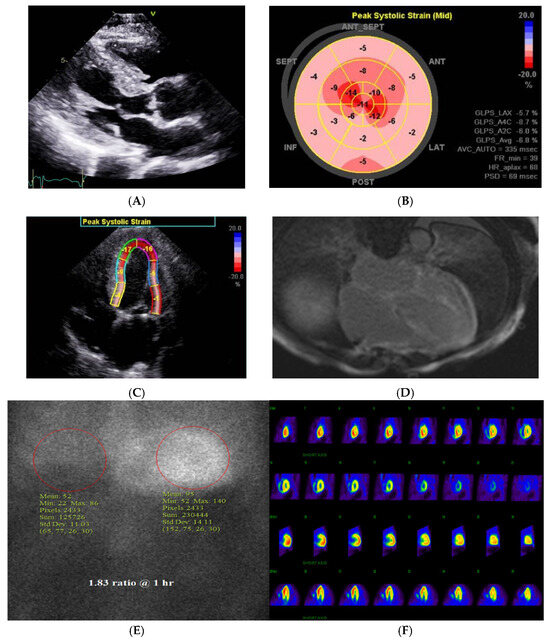

- Bukhari, S.; Bashir, Z. Diagnostic Modalities in the Detection of Cardiac Amyloidosis. J. Clin. Med. 2024, 13, 4075. [Google Scholar] [CrossRef]

- Bashir, Z.; Musharraf, M.; Azam, R.; Bukhari, S. Imaging modalities in cardiac amyloidosis. Curr. Probl. Cardiol. 2024, 49, 102858. [Google Scholar] [CrossRef]